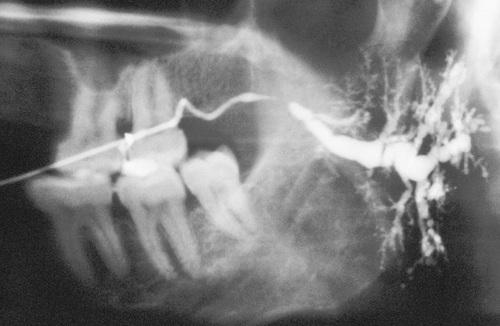

Radiopaque mass located at the left angle of the mandible. They may be discovered anywhere along the length of the duct or within the gland itself.

sialolith

- Periapical film showing discrete radiopacity superimposed on the body of the mandible. Care must be taken not to confuse this with intrabony pathosis.

- Occlusal radiograph of same patient demonstrating radiopaque mass in Wharton duct.